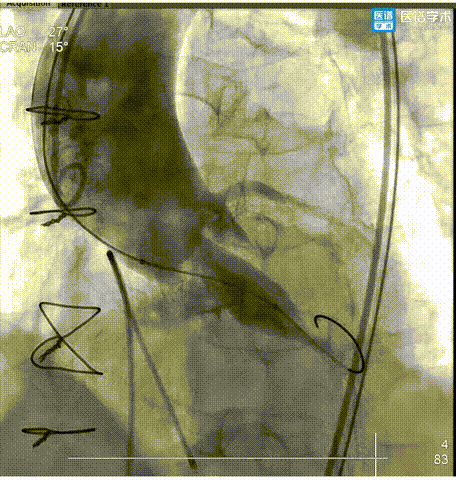

6.瓣膜释放至工作位后,造影评估示瓣膜植入较深,遂行完全回收重定位再释放。

7. 第二次释放后,经多投照角度评估,瓣膜仍存在植入过深情况,遂进行第二次完全回收重定位再释放。